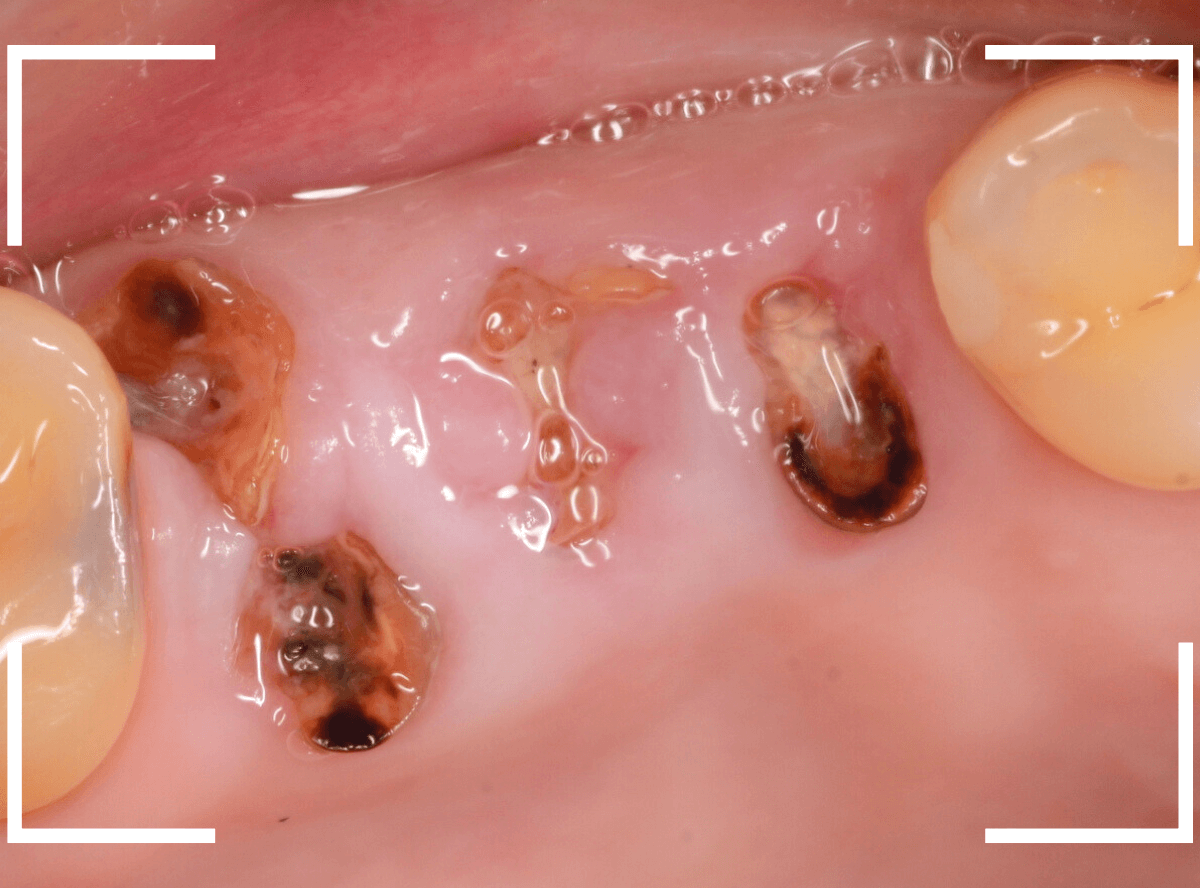

Case.5 残根状態の歯の抜歯3

今回も、根っこだけ残ってしまった状態の歯の抜歯ケースです。

歯肉の外にわずかに歯の部分が露出している状態です。

レントゲン写真で確認します。

へし折れてしまっている根もありますが、わりとはっきり根の状態がレントゲンに写ってますので、抜きやすい状態かもしれません。

何とか、短時間で無事に抜くことができました。

問題は、「抜歯後にどう噛めるようにしていくか」ですね。

経過観察後、患者さんと相談になりますが、このような状態にならないように、皆さんも気をつけてくださいね。